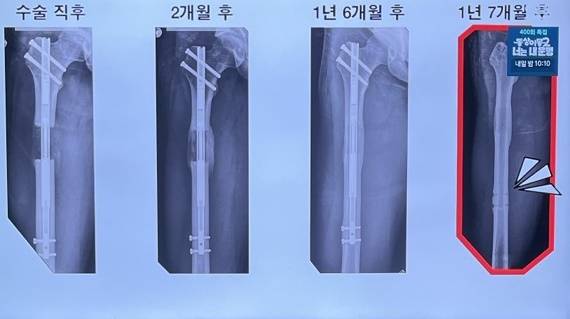

![사지연장술 수술 후 경과. [사진=SBS]](https://img2.daumcdn.net/thumb/R658x0.q70/?fname=https://t1.daumcdn.net/news/202508/11/KorMedi/20250811120716526qovn.jpg)

수술 및 안정화 시기를 거쳐 초기 뼈 재생을 유도하는 지연기(latency)를 지나 뼈가 하루 1mm씩 확장하는 신장기(distraction phase), 뼈 조직이 단단해질 때까지 고정 유지하는 경화기(consolidation)로 이어진다. 몇 개월에서 몇 년에 걸친 회복이 필요할 수 있다.